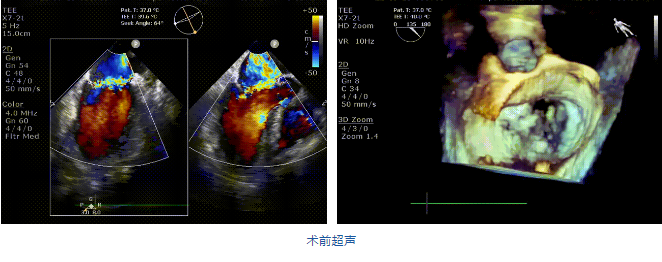

接受治療的是一例二尖瓣重度反流的患者,主訴“突發(fā)間歇性胸悶,氣急6天”。術(shù)前超聲提示:1.二尖瓣脫垂伴重度關(guān)閉不全(瞬時量30ml);2.左心、右房增大(左房容積110ml,左室容積129ml,右房容積55ml);3.左室收縮功能正常。患者在充分標(biāo)準(zhǔn)化藥物治療后(GDMT)仍然癥狀明顯,韓林教授及其團隊唐楊烽教授,以及心超科的周廣為醫(yī)生決定使用我國創(chuàng)新器械JensClip為患者進(jìn)行二尖瓣緣對緣修復(fù)手術(shù)。

在阜外醫(yī)院潘湘斌教授團隊的支持下,手術(shù)經(jīng)股靜脈-房間隔入路,采用全身麻醉插管,在TEE和DSA引導(dǎo)下完成房間隔穿刺。置入JensClip瓣膜夾系統(tǒng)后,在左房調(diào)整瓣膜夾的位置和軸向,后進(jìn)入左室,在TEE引導(dǎo)下捕捉二尖瓣前后瓣葉,并關(guān)閉瓣膜夾。經(jīng)TEE反復(fù)確認(rèn)手術(shù)效果后最終鎖定并釋放瓣膜夾。術(shù)后即刻超聲顯示瓣膜夾位置穩(wěn)定,功能良好,二尖瓣反流由術(shù)前4+減少至微量,手術(shù)圓滿成功。